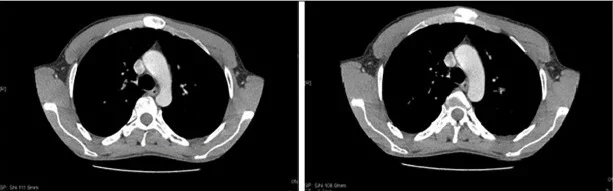

Компютърна томография, показваща хипертрофия с хиподензен вид на хрущялите на първата, втората и третата стернокостални стави в ляво.

Изображние: sciencedirect.com/CC BY-NC-ND 4.0